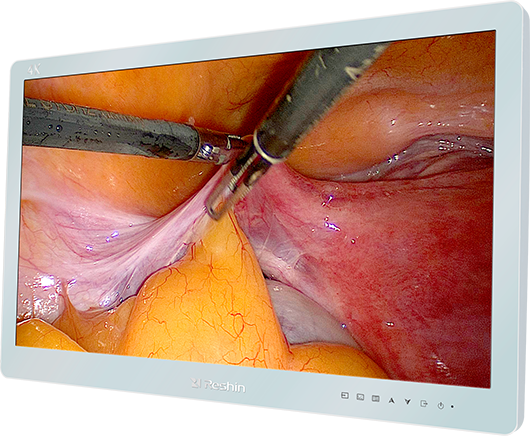

手术室对医疗显示器清晰度的要求很高。睿显27英寸手术医疗显示器采用4K超高清屏,在保证手术画面超清晰的同时,有效降低反光带给医生的不适感。具备多信号接口,适应于多种图像显示,特别配置12G-SDI模块,支持真4K超高清显示,配备专业的SDI线,可支持超过50米以上的超长距离、无压缩传输,布线简单、抗干扰能力强,非常适合于手术室环境的应用。